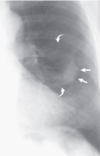

Fig. 3.5 Atelectasia redonda en un hombre con enfermedad pleural relacionada con el amianto. Una vista ampliada del pulmón izquierdo de una radiografía de tórax posteroanterior muestra una opacidad ovalada. Los márgenes laterales (flechas rectas) están bien definidos (donde la opacidad linda con el pulmón) y los márgenes mediales están mal definidos (donde la opacidad linda con la pleura). Se puede ver que los vasos pulmonares (flechas curvas) se curvan hacia la opacidad (signo de la cola del cometa)